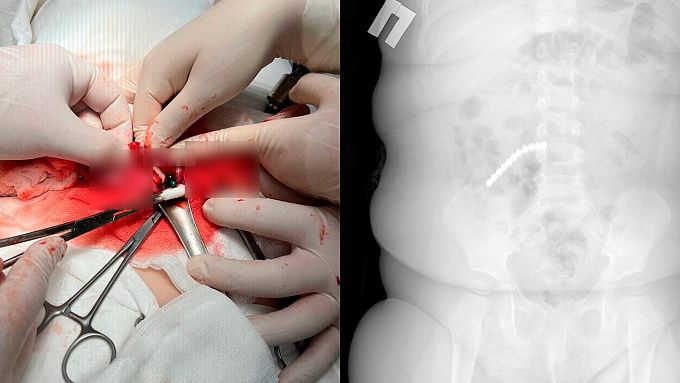

Ребенок поступил в ДРКБ в начале февраля с рвотой и ухудшением состояния. На рентгене врачи увидели множество инородных тел в пищеварительном тракте. Снимок показал 20 магнитных шариков от неокуба.

- Нам удалось удалить девять штук магнитов эндоскопически (ФГДС). Однако остальные мигрировали по кишечнику, вызвав перфорацию. Петли тонкой, сигмовидной и слепой кишки слиплись между собой из-за магнитного притяжения, — пояснил врач-хирург-эндоскопист ДРКБ Булат Шагдаров.

Ситуация потребовала немедленной открытой операции. Ребенку провели лапаротомию. Хирурги ушили образовавшиеся межкишечные свищи, удалили участок тонкой кишки с перфорацией размером до 2 см. Часть магнитов опустилась в аппендикс, его также пришлось удалить.